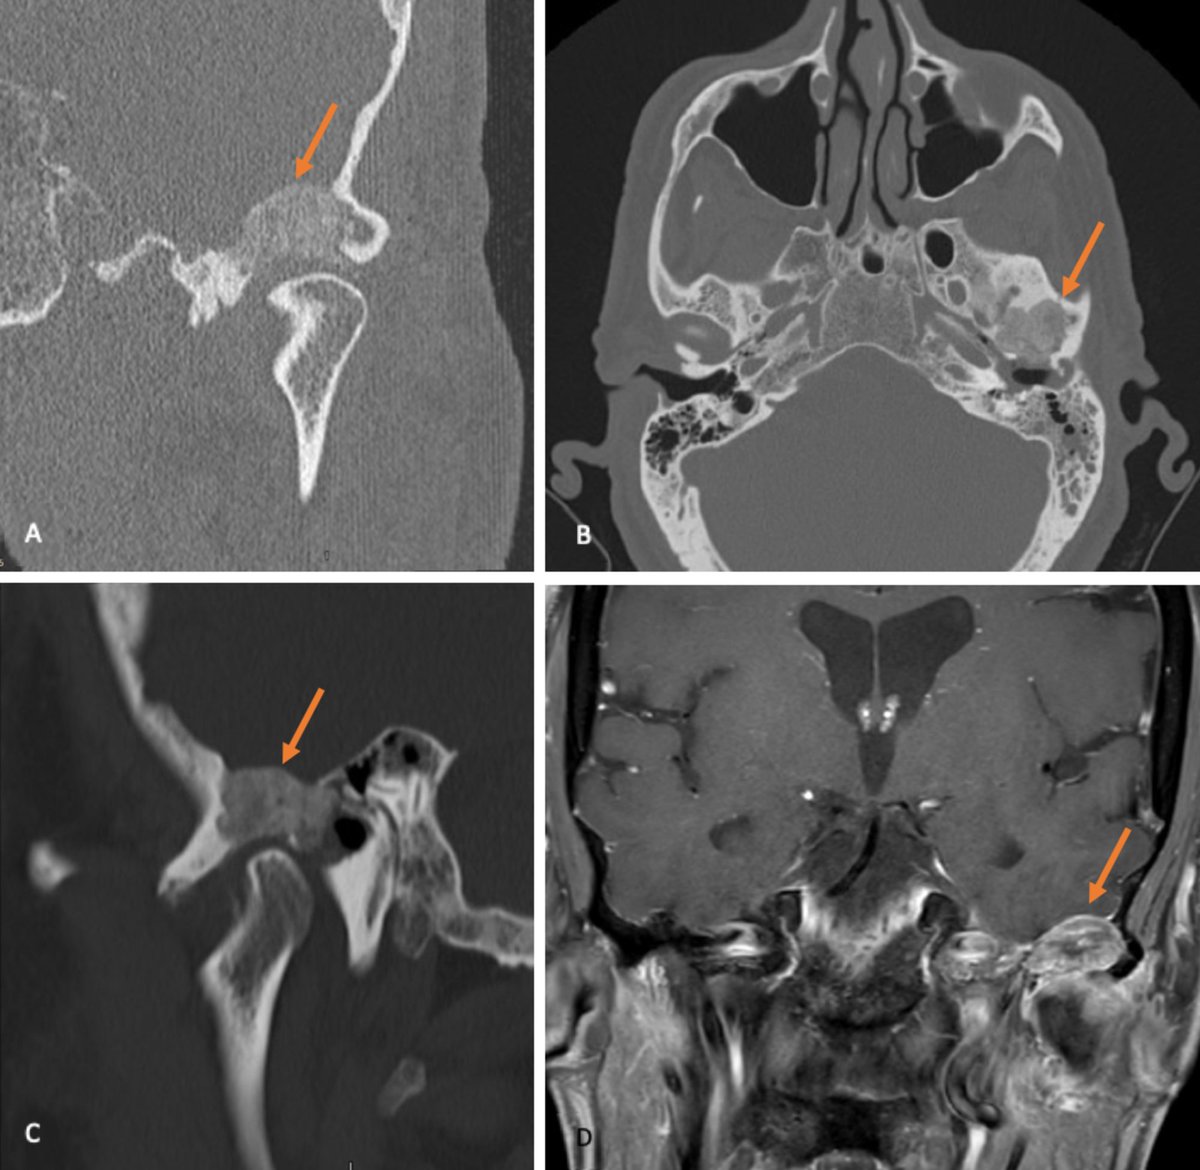

هشاشة #العظام. #الرومتويد. التهاب المفاصل. تاكل #الغضاريف

5• حصوات كلى #تصلب شرايين تكلسات ومشاكل #الركبة والمفاصل ضعف الاسنان هشاشة عظام.

وهنا ياتي دور السيكا والسلكا دورها انها تدخل في العظام والمفاصل في الاماكن التي تحتاج بناء وعلاج وتعمل ذبذبات او نبضات كهربائية لتنجذب المعادن في هذه النقطة وتجتمع البوتاسيوم الفسفور الكالسيوم البرورون والمغنيسيوم

12•كل هذه المعادن #تنجذب وتدخل في العظم بسبب #السيلكا ويتم اصلاح المشكلة سواء في العظم او المفصل او الاسنان